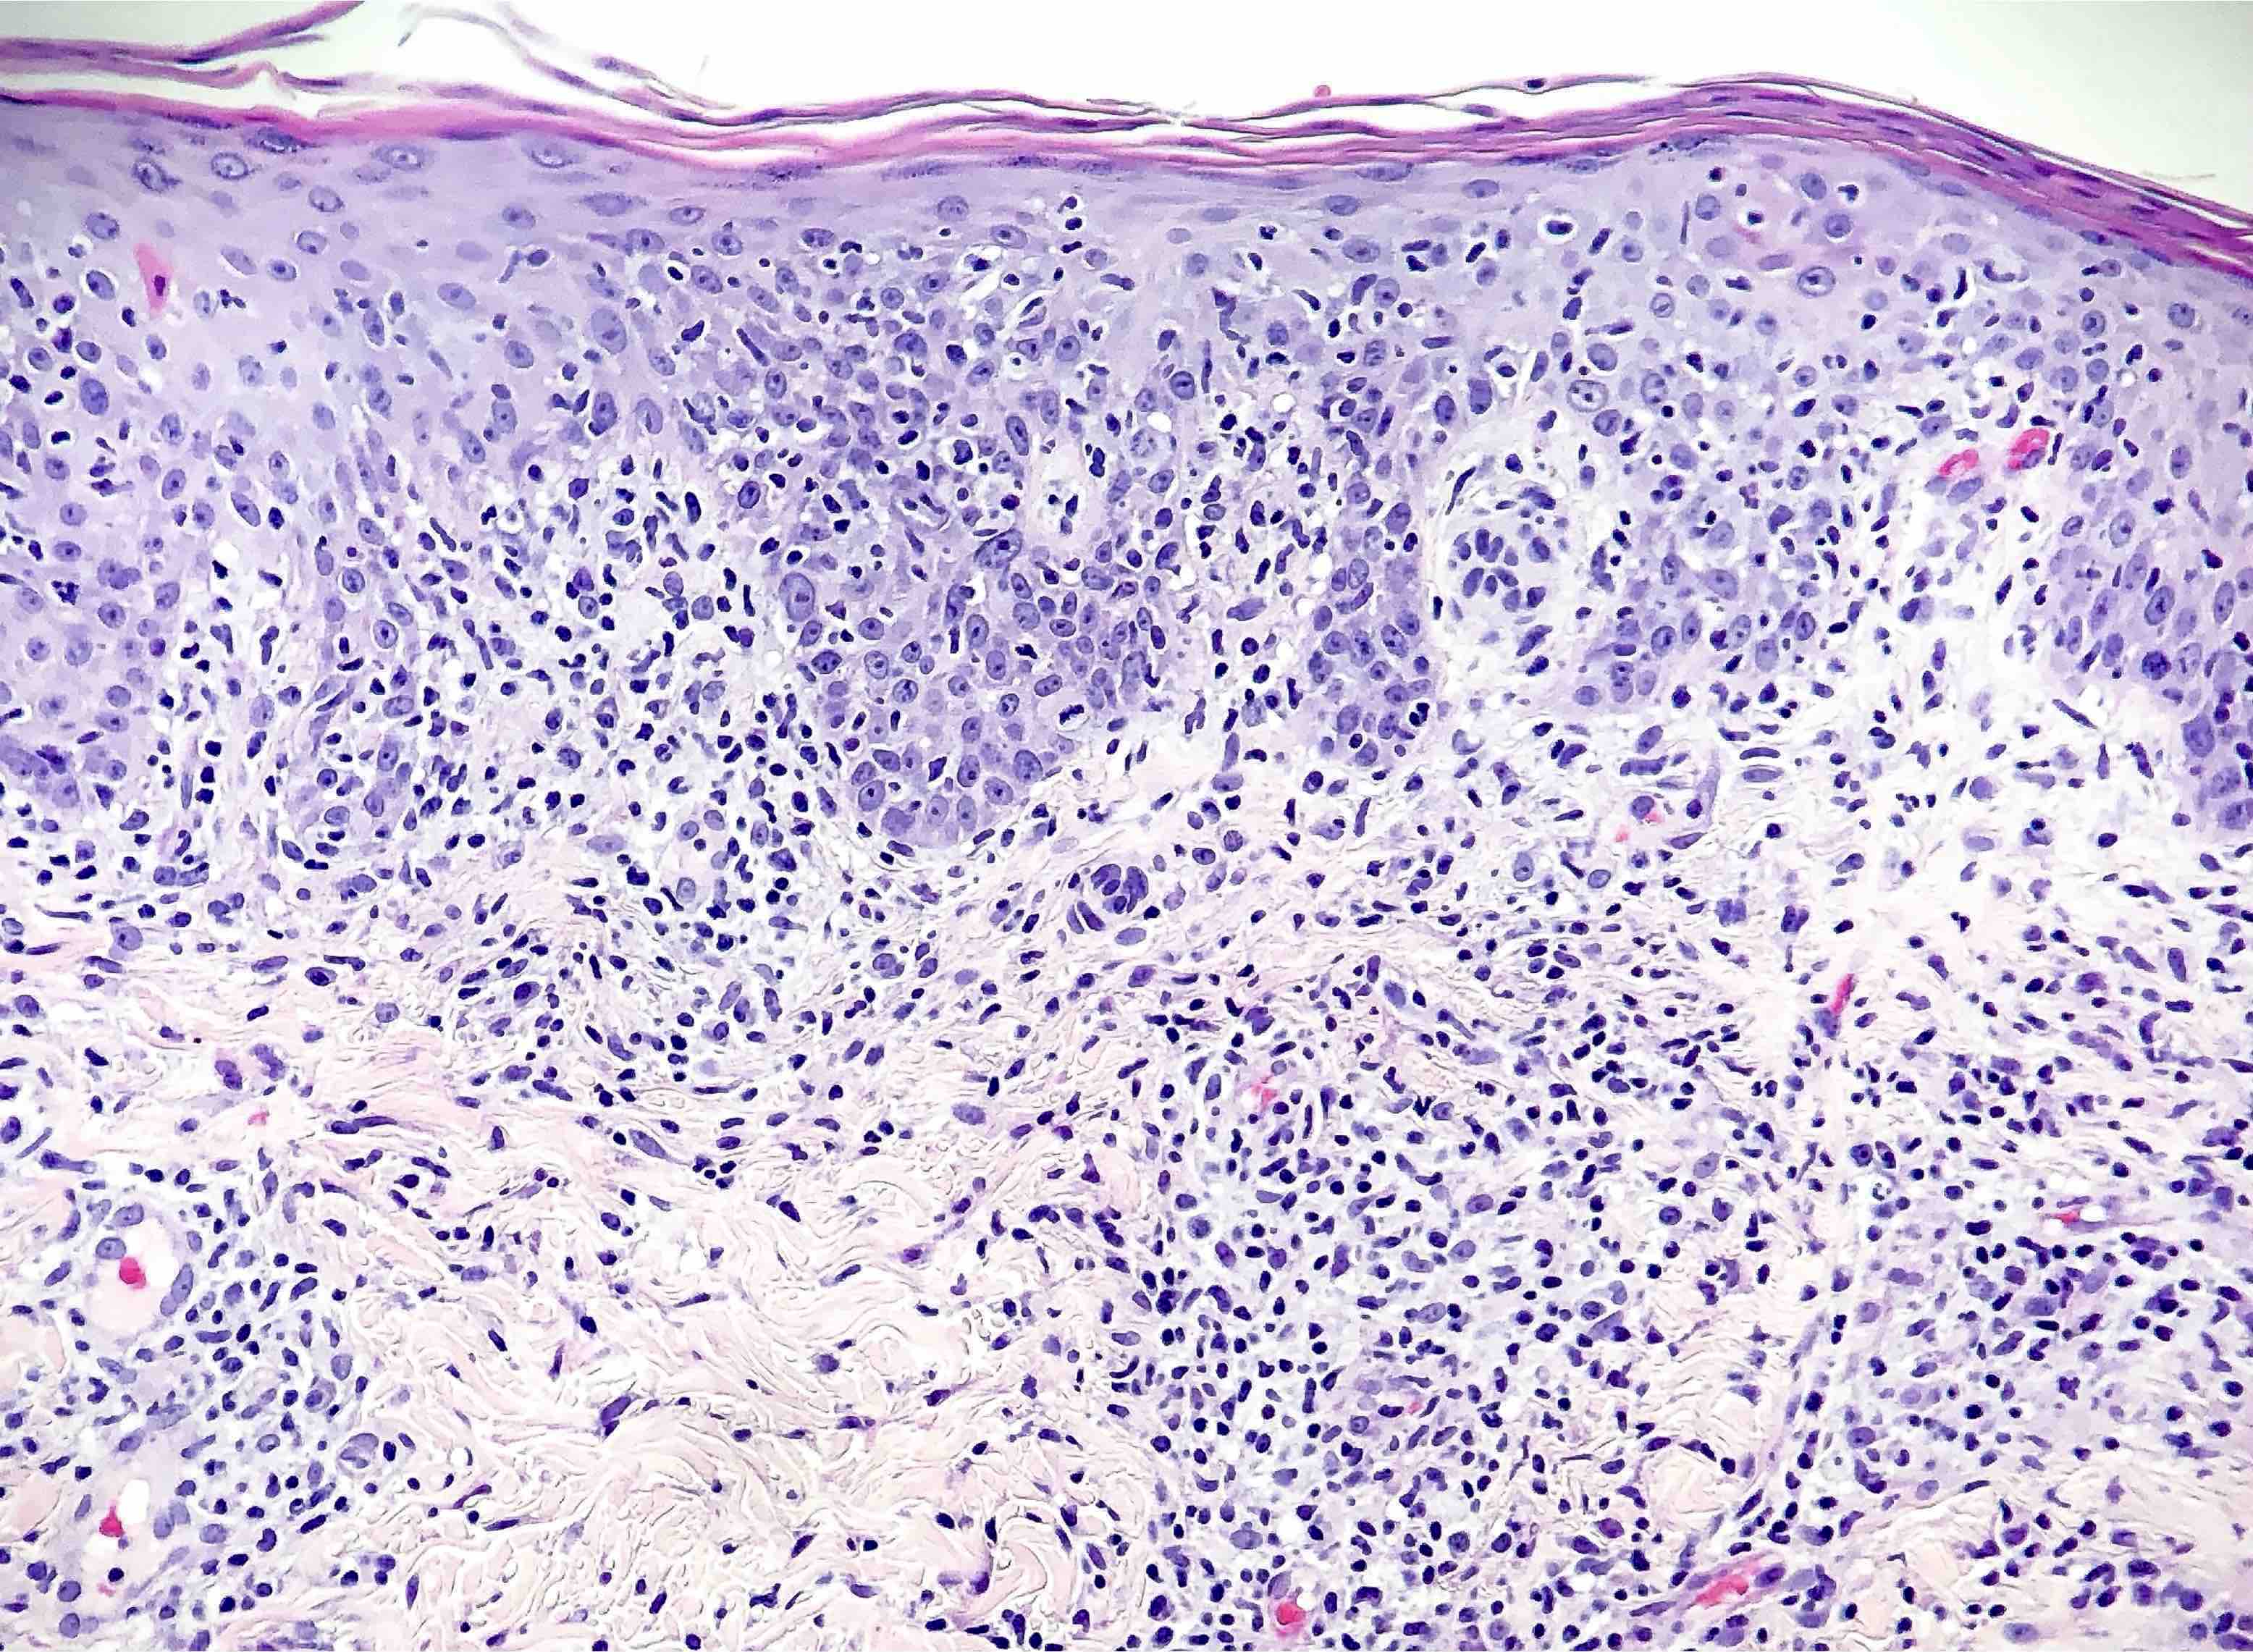

- Secondary syphilis:

- Lichenoid superficial and deep perivascular and periadnexal lymphohistiocytic inflammation with admixed plasma cells

- Plasma cells may be absent in 33% of biopsies

- Eosinophils can be present

- Marked endothelial swelling and proliferation of blood vessels can be seen

- Commonly identified are vacuolar interface change, acanthosis or lymphocyte exocytosis

- In late secondary syphilis, granulomatous inflammation may be present

- Microabscess formation of the hair follicle has also been seen